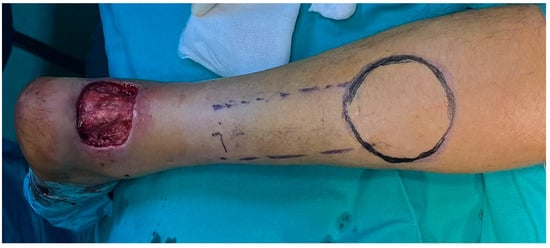

The soft tissue defect was treated with a local reverse sural flap. The pedicle of the flap was 4 cm wide. The flap was dissected, and the pedicle was dissected, and the flap was pivoted to the defect through a tunnel under the skin. The tunnel was performed in the supra-fascial plane, 9 cm long and 5 cm wide. The donor site was covered with STSG. Postoperatively, there was no concern regarding the blood flow to the flap. Figure 11.

Unexpectedly, 2 weeks after surgery, a superficial necrosis of the skin area developed over the pedicle flap (5 cm × 5 cm), with a marginal area of necrosis (1 cm × 0.5 cm). Because it was superficial, it was treated only with local dressings. Although usually the flap is affected by vascular insufficiency, in our case, the complication developed at the level of the skin over the tunnel. It appeared around 10 days after the fix and flap surgery, and the area healed under conservative treatment in about 2 weeks. Figure 12.

Figure 11. Intraoperative design of the flap.

Figure 12. (A) follow-up picture at 4 days postoperatively. The area above the tunnel has a modified color, signaling the local suffering. (B) 2 weeks follow-up picture. The area of superficial necrosis over the tunnel can be shown.